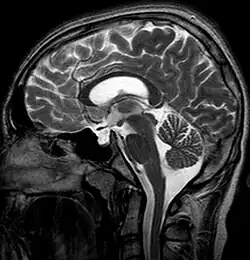

MRI is the gold standard for diagnosing the empty sella sign. Key features include:[5]

- CSF signal: The sella turcica is filled with material that follows the signal characteristics of CSF on T1-weighted and T2-weighted images.

- Flattened pituitary gland: The pituitary gland appears thin and plastered against the sellar floor or walls.

- Enlarged sella: The sella turcica may appear expanded or normal in size.